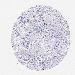

SKIN CANCER - Protein expressioni

A mouse-over function shows sample information and annotation data. Click on an image to view it in a full screen mode. Samples can be filtered based on level of antibody staining by selecting one or several of the following categories: high, medium, low and not detected. The assay and annotation is described here.

Each image is clickable and will lead to virtual microscopy that enables deeper exploration of all samples and also displays staining intensity scores, fraction scores and subcellular localization as well as patient and tissue information for each sample.

Antibody CAB001452

Basal cell carcinoma